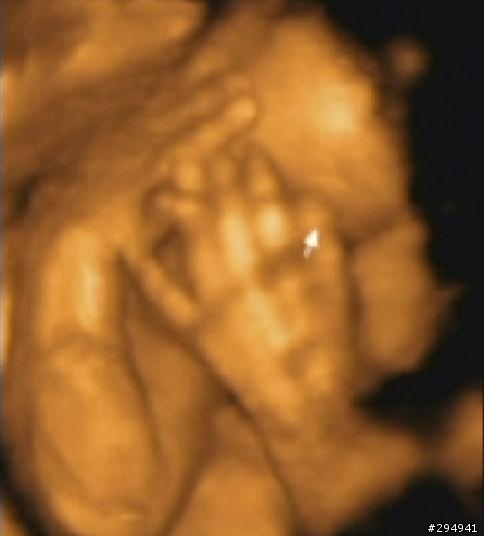

今天要為各位介紹的是4D超音波 , 啥? 為何叫4D喔 ? 簡單的說 1D是線(X軸) , 2D是面(X-Y軸) ,

3D是立體(X-Y-Z軸) , 4D 就是 3D加上時間軸向 (又可稱為W軸) .

啥? 還是看不懂 , 簡單的說 , 4D 就是會動的3D圖像 , 只是增加了聲音與動態 , 這樣簡單吧.

========= 開始4D分享 =========

第五彈 , 千呼萬喚始出來 (口愛吧)